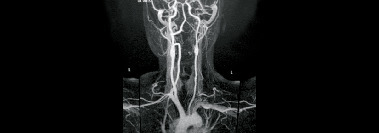

Maladie de Takayasu

Vascularite granulomateuse de l’aorte et de ses principales branches également (fig. 2), elle affecte les sujets de moins de 50 ans. Après une phase systémique (fièvre, arthralgies, syndrome inflammatoire) surviennent les manifestations vasculaires ischémiques secondaires aux sténoses. Si l’atteinte de l’aorte et des troncs supra-­aortiques (principalement les artères sous-clavières) [fig. 3] est la plus fréquente, toutes les autres artères (rénales, mésentériques, pulmonaires, des membres inférieurs…) peuvent être concernées. Le diagnostic fait appel à l’imagerie (Doppler, angioscanner, imagerie par résonance magnétique [IRM], tomographie par émission de positons [TEP scanner]…) mettant en évidence un épaississement inflammatoire des parois artérielles et des sténoses (fig. 4). Le traitement est fondé sur la corticothérapie et les biothérapies. La radiologie interventionnelle (angioplastie percutanée...) et la chirurgie vasculaire peuvent être nécessaires en cas de sténoses (tableau 3).